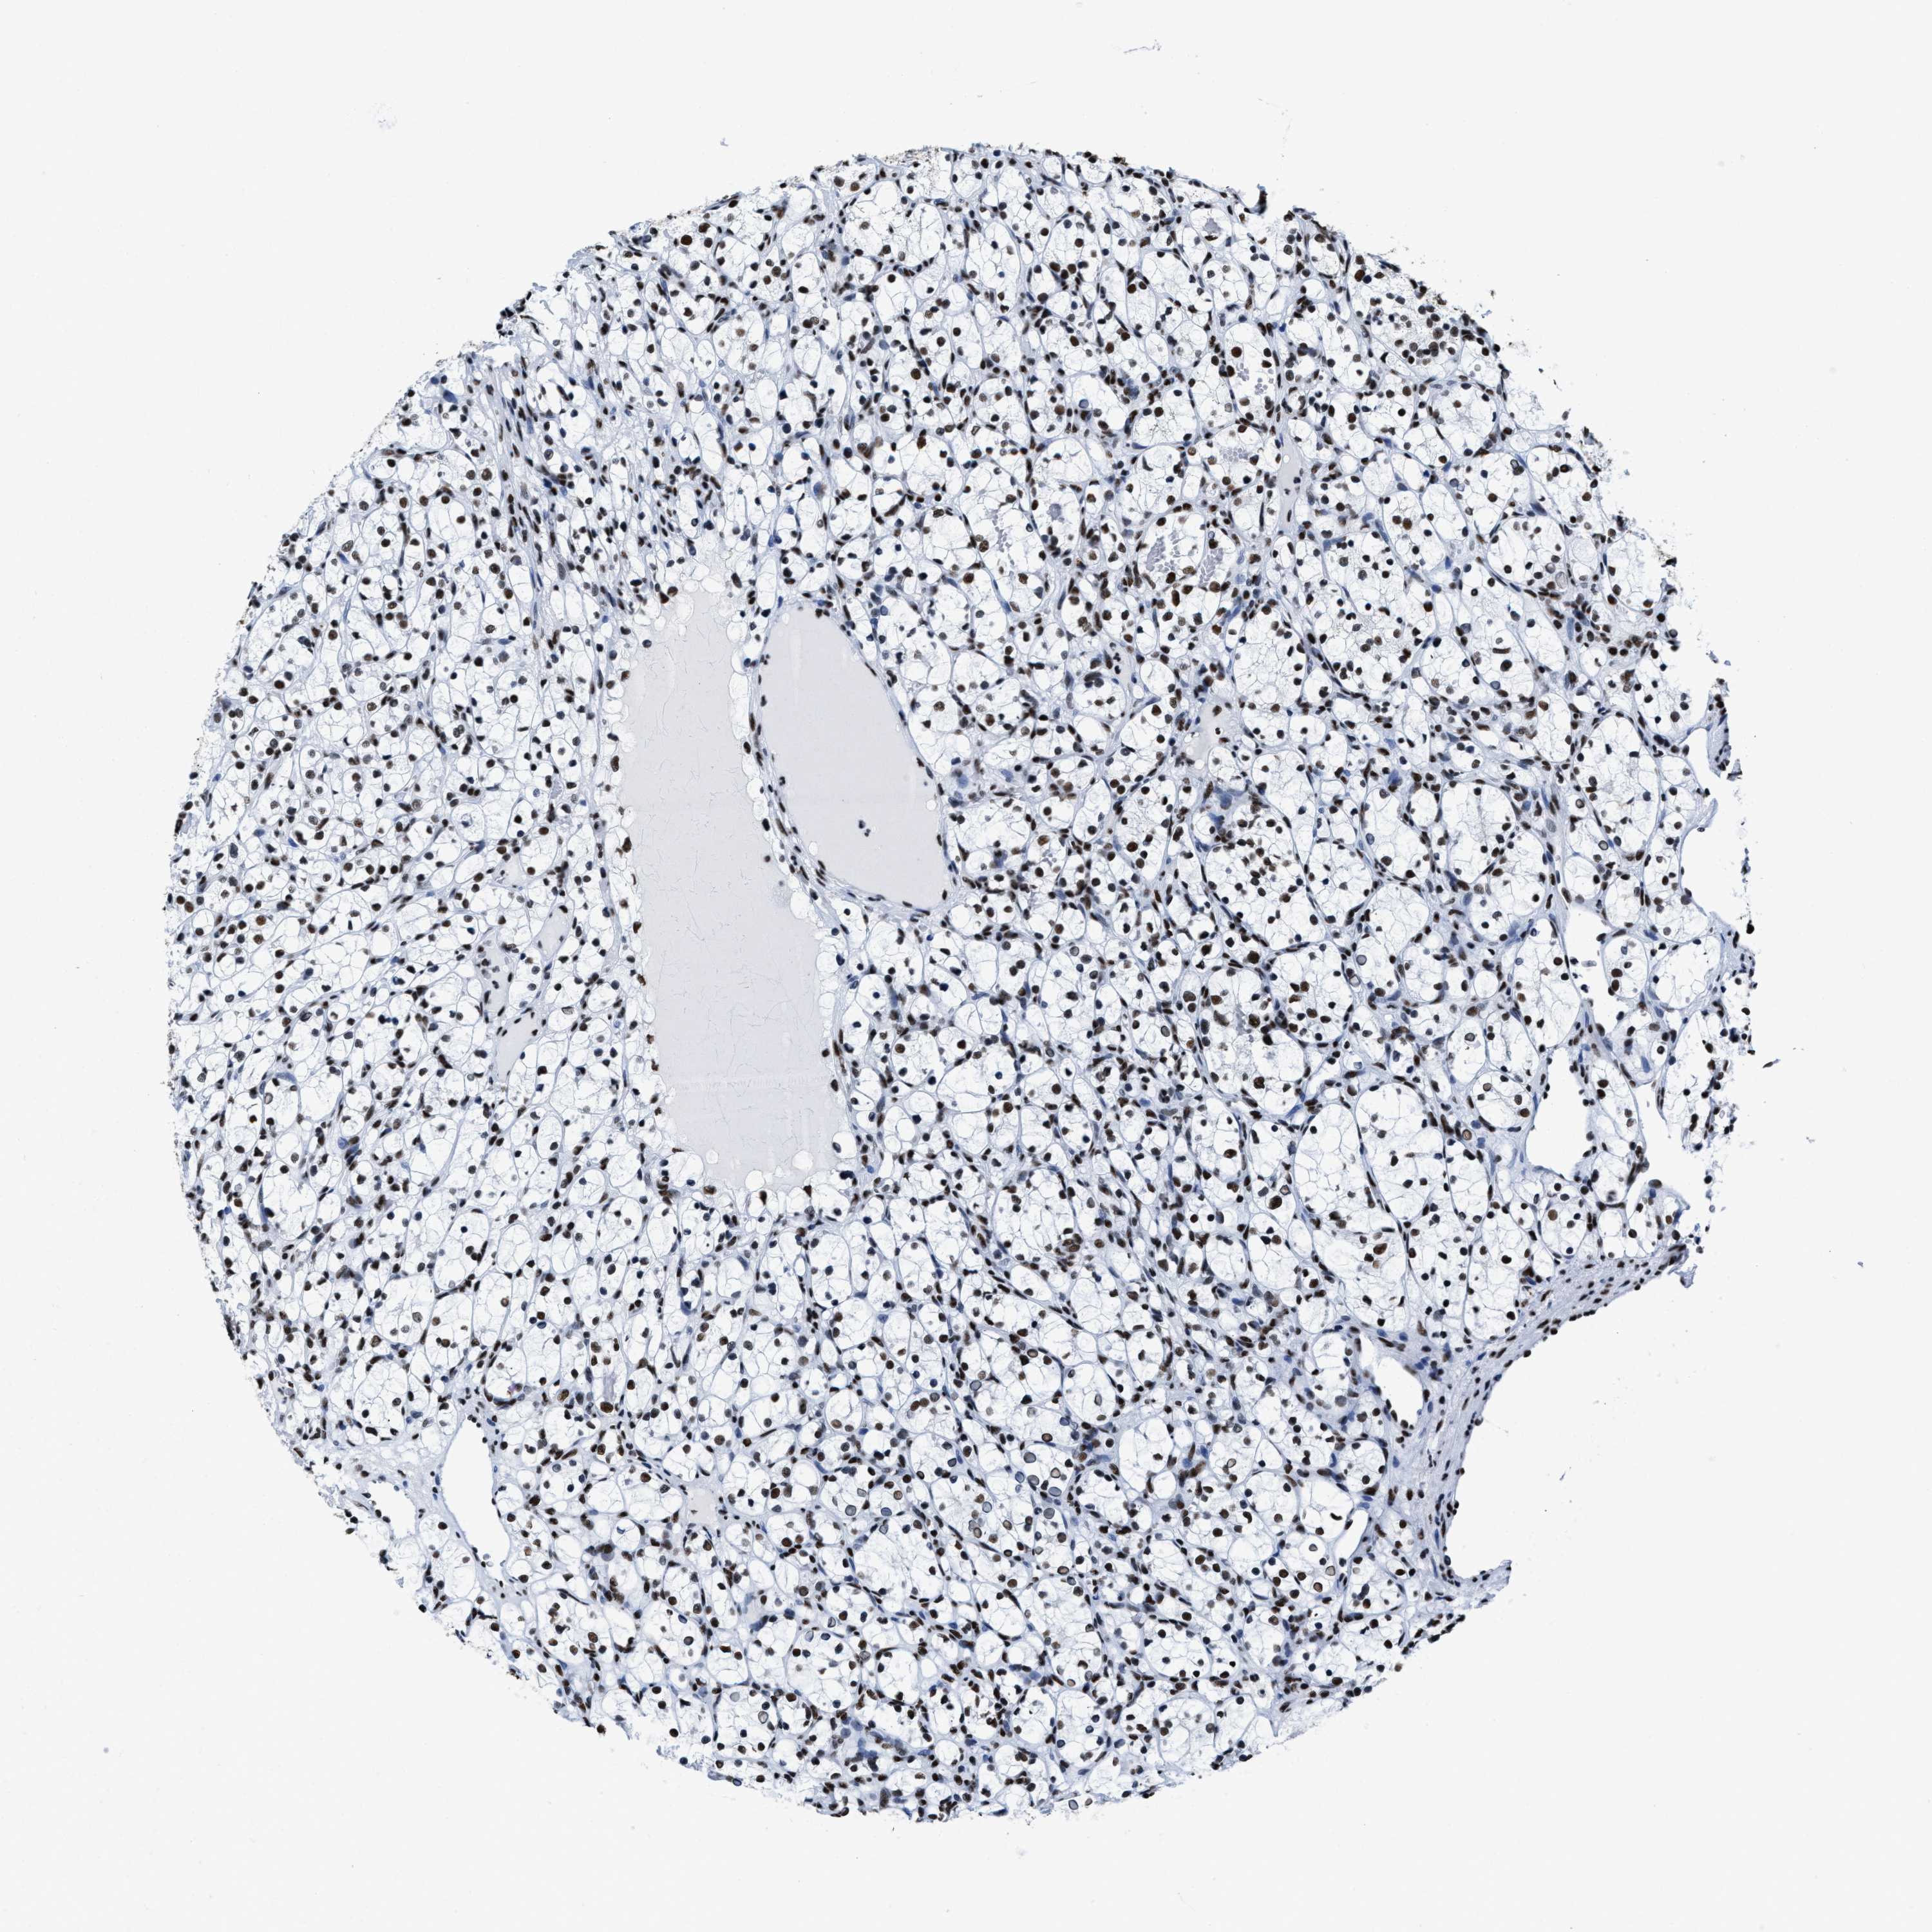

KIDNEY RENAL CLEAR CELL CARCINOMA (VALIDATION) - Interactive survival scatter ploti

The Survival Scatter plot shows the clinical status (i.e. dead or alive) for all individuals in the patient cohort, based on the same data that underlies the corresponding Kaplan-Meier plots. Patients that are alive at last time for follow-up are shown in blue and patients who have died during the study are shown in red.

The x-axis shows the expression levels (FPKM) of the investigated gene in the tumor tissue at the time of diagnosis. The y-axis shows the follow-up time after diagnosis (years). Both axes are complimented with kernel density curves demonstrating the data density over the axes. The top density plot shows the expression levels (FPKM) distribution among dead (red) and alive patients (blue). The right density plot shows the data density of the survived years of dead patients with high and low expression levels respectively, stratified using the cutoff indicated by the vertical dashed line through the Survival Scatter plot. This cutoff is automatically defined based on the FPKM cutoff that minimizes the p-score. The cutoff can be changed by dragging the vertical line or by entering a cutoff value in the square labeled "Current cut-off".

Under the Survival Scatter plot the p-score landscape (black curve; left axis) is shown together with dead median separation (red curve; right axis). Dead median separation is the difference in median mRNA expression between patients who have died with high and low expression, respectively. It is calculated as follows: median FPKM expression of dead patients with high expression - median FPKM expression of dead patients with low expression. This is intended to aid the user in visually exploring custom cutoffs and the associated p-scores and dead median separation.

Individual patient data is displayed and can be filtered by clicking on one or more of the category buttons on the top of the page. Categories describing expression level and patient information include: high, low, alive, dead, female, male and tumor stages. The scale of the x-axis can be toggled between linear and log-scale by clicking on the "x log" button. Mouse-over function shows TCGA ID, patient information and mRNA expression (FPKM) for each patient.

& Survival analysisi

Kaplan-Meier plots summarize results from analysis of correlation between mRNA expression level and patient survival. Patients were divided based on level of expression into one of the two groups "low" (under cut off) or "high" (over cut off). X-axis shows time for survival (years) and y-axis shows the probability of survival, where 1.0 corresponds to 100 percent.

SMARCC2 is not prognostic in Kidney Renal Clear Cell Carcinoma (validation)

Best expression cut offi

Based on the FPKM value of each gene, patients were classified into two groups and association between prognosis (survival) and gene expression (FPKM) was examined. The best expression cut-off refers the FPKM value that yields maximal difference with regard to survival between the two groups at the lowest log-rank P-value. Best expression cut-off was selected based on survival analysis .

When clicking on this number, the vertical dashed line indicating cut-off, the interactive survival plot, and the Kaplan-Meier curve will be adjusted to show results based on the best expression cut-off.

: 44.04

P scorei

Log-rank P value for Kaplan-Meier plot showing results from analysis of correlation between mRNA expression level and patient survival.

N/A

5-year survival highi

5-year survival for patients with higher expression than the expression cutoff.

For melanoma and glioma, 3-year survival is shown.

5-year survival lowi

5-year survival for patients with lower expression than the expression cutoff.

TCGA RNA samplesi

RNA-seq data is reported as average FPKM (number Fragments Per Kilobase of exon per Million reads), generated by the The Cancer Genome Atlas (TCGA) .

Normal distribution across the dataset is visualized with box plots, shown as median and 25th and 75th percentiles. Points are displayed as outliers if they are above or below 1.5 times the interquartile range. FPKM values of the individual samples are presented next to the box plot.

Average pTPM 43.8

Number of samples 100